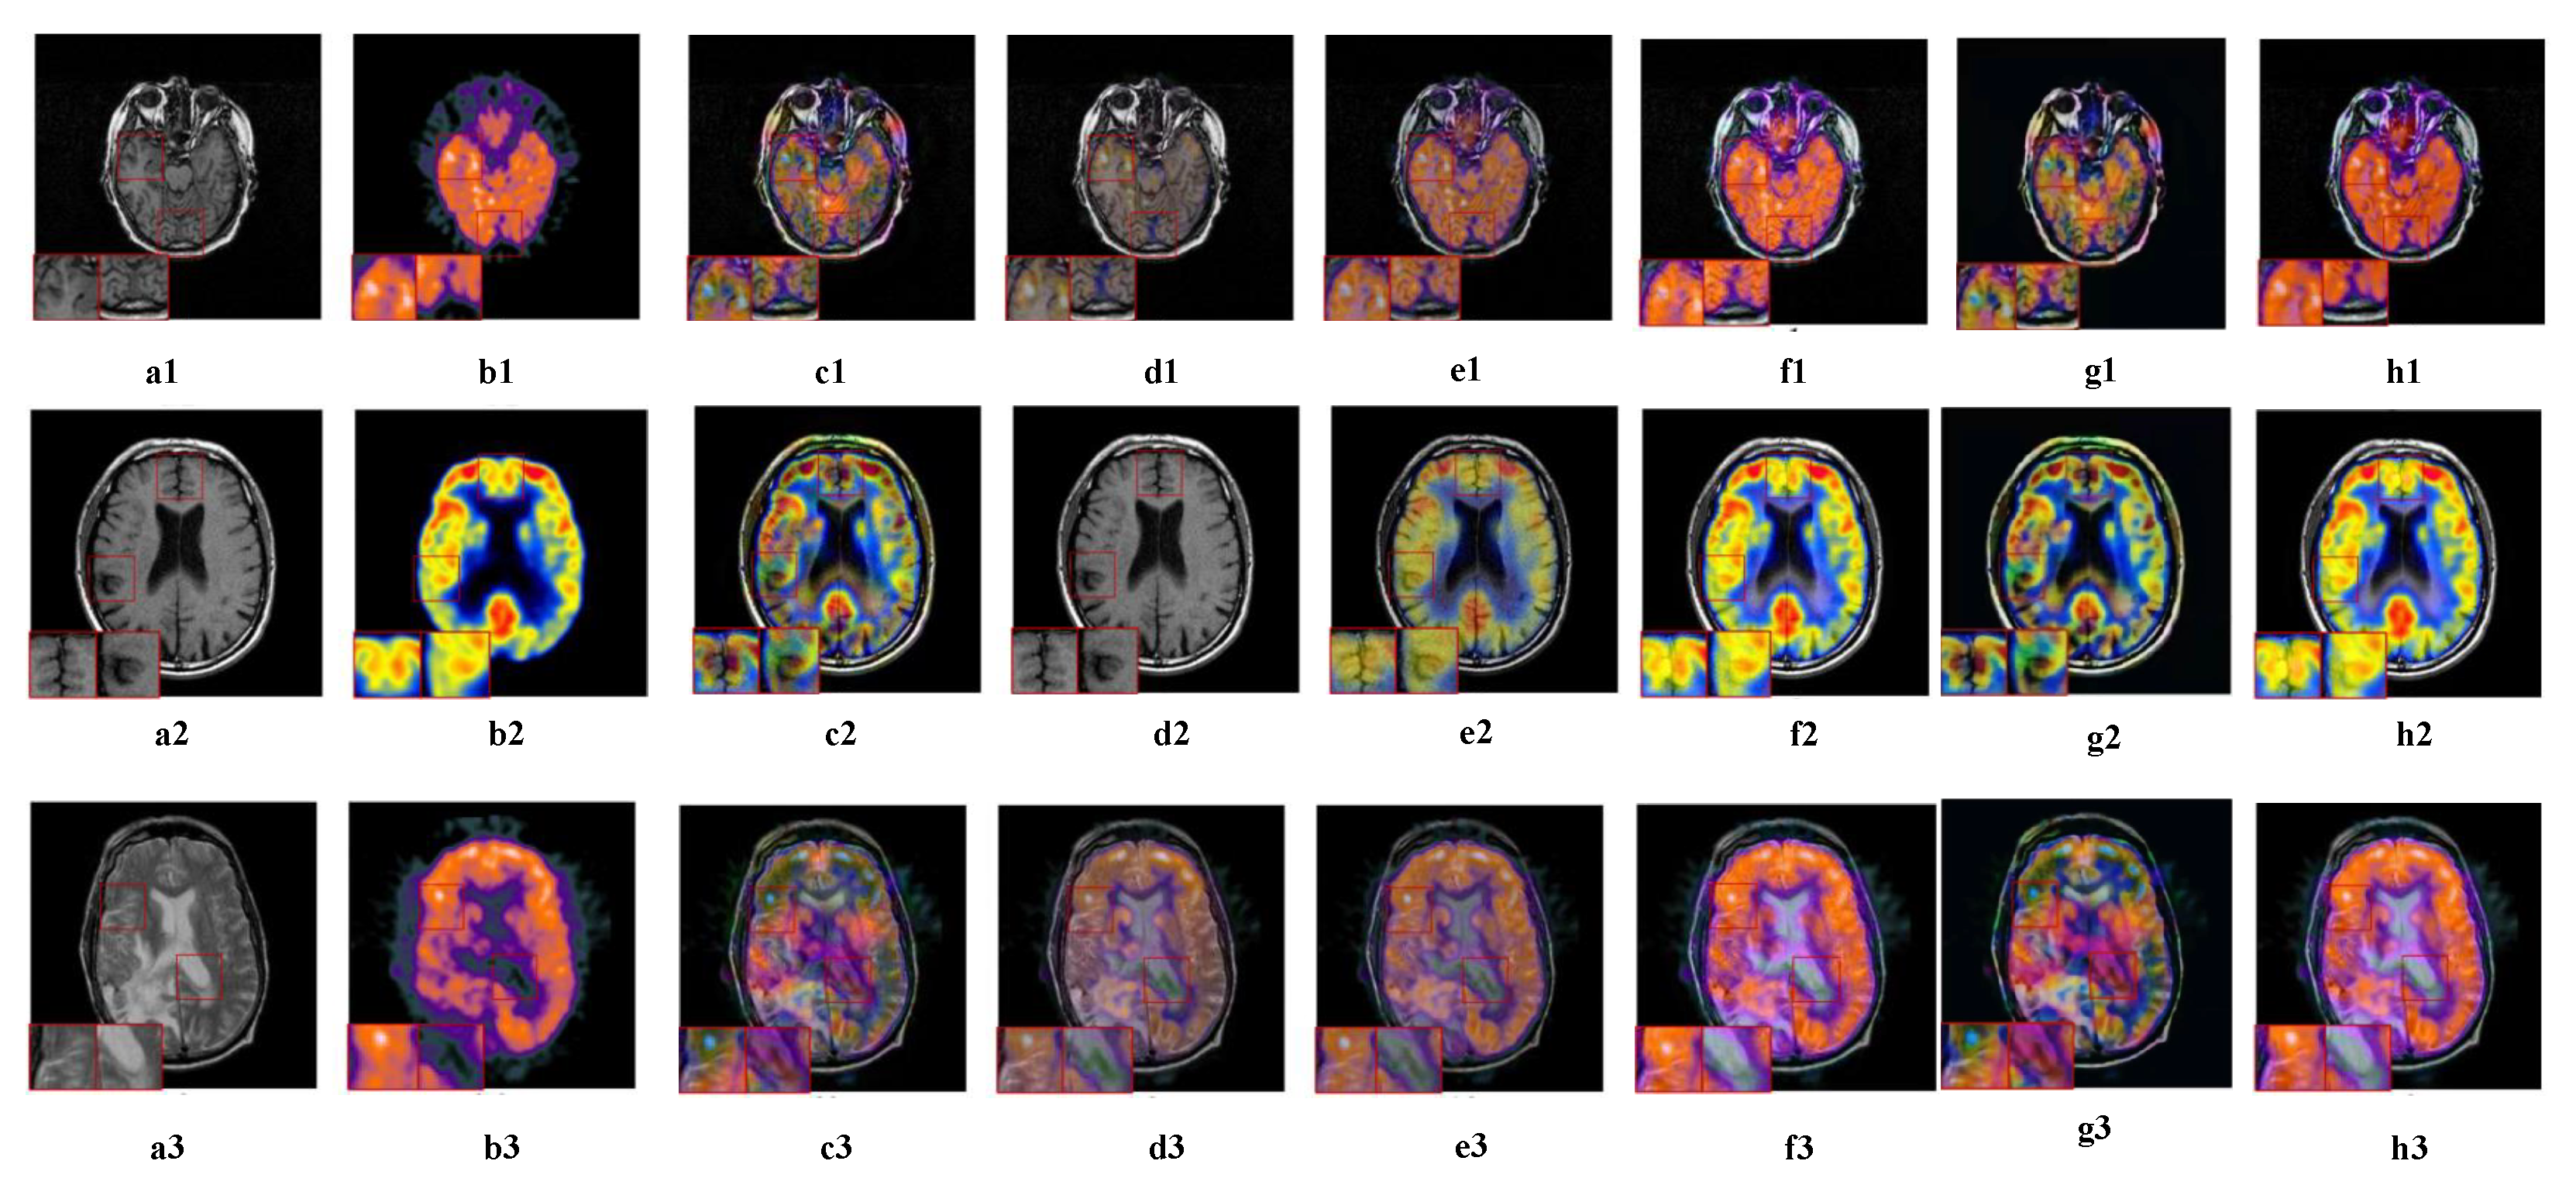

5.2.4. Fusion Analysis on MRI-PET